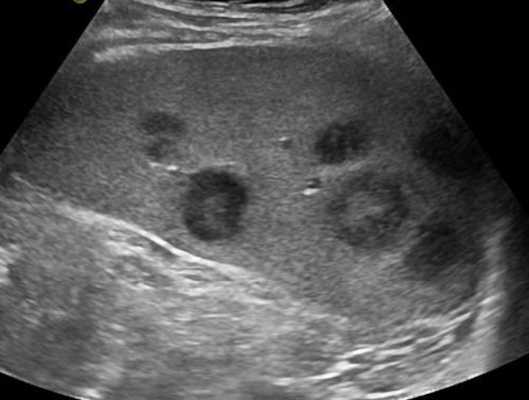

При повторных УЗ осмотрах на фоне массированной противовоспатительной терапии было отмечено увеличение числа лимфатических узлов вовлеченных в процесс активизации. При этом заметной перестройки эхоструктуры и уменьшения размеров в наблюдаемых лимфатических узлах отмечено не было (рис 4).

Рис. 4. Варианты изображения увеличенного лимфатического узла с УЗ-признаками доброкачественной аденопатии у больного с синдромом иммунодефицита.